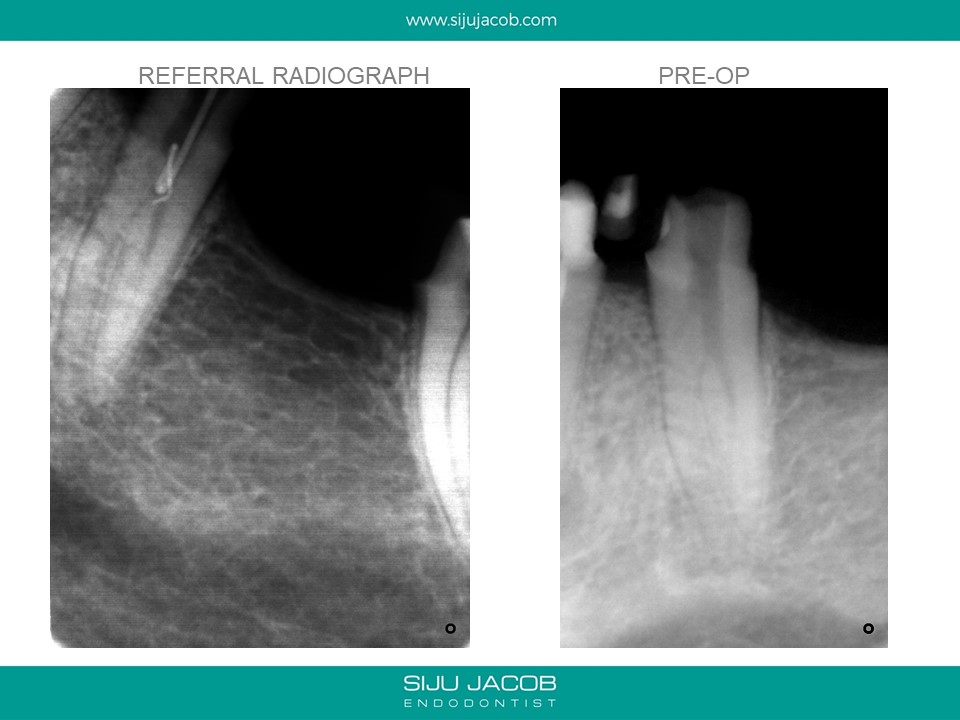

This was referred by a clinician who started the case thinking it was a regular premolar. Looking at the radiograph that the referral e-mailed me, I was expecting a Two-canalled premolar. The master-cone radiograph showed the lack of centricity of the two canals i had discovered. I went back in and found the third canal.